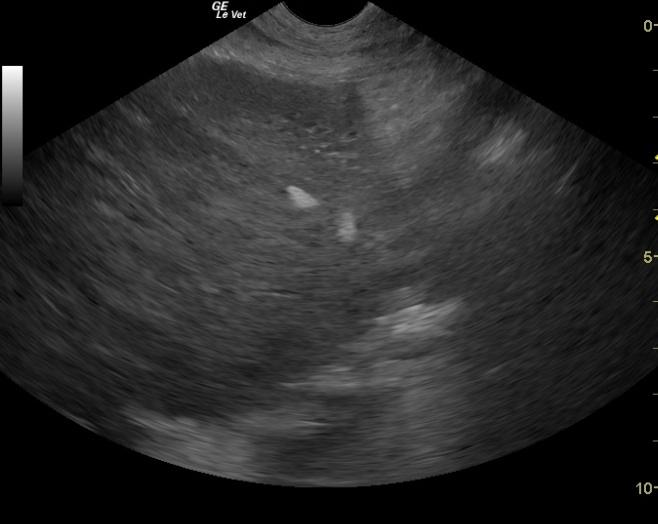

A 10-year-old MN Elkhound dog with a history of chronically elevated liver values nd p[ast episodes of hepatitis. He presented for possible foreign body ingestion, protracted vomiting, anorexia, and decreased activity. Physical examination was non-remarkable. Urine specific gravity was within normal limits. Abnormalities on CBC and blood chemistry were leukocytosis, monocytosis, increased basophils, mild azotemia, hyperkalemia, elevated total protein, mild hyperalbuminemia, and elevated ALP activity. Radiographs showed urinary calculi, distended stomach, and a questionable pattern in the small intestines. The patient was treated with subcutaneous fluids, cerenia, and famotidine. exploratory surgery had been performed for GI foreign body and the sonogram was performed post-op.